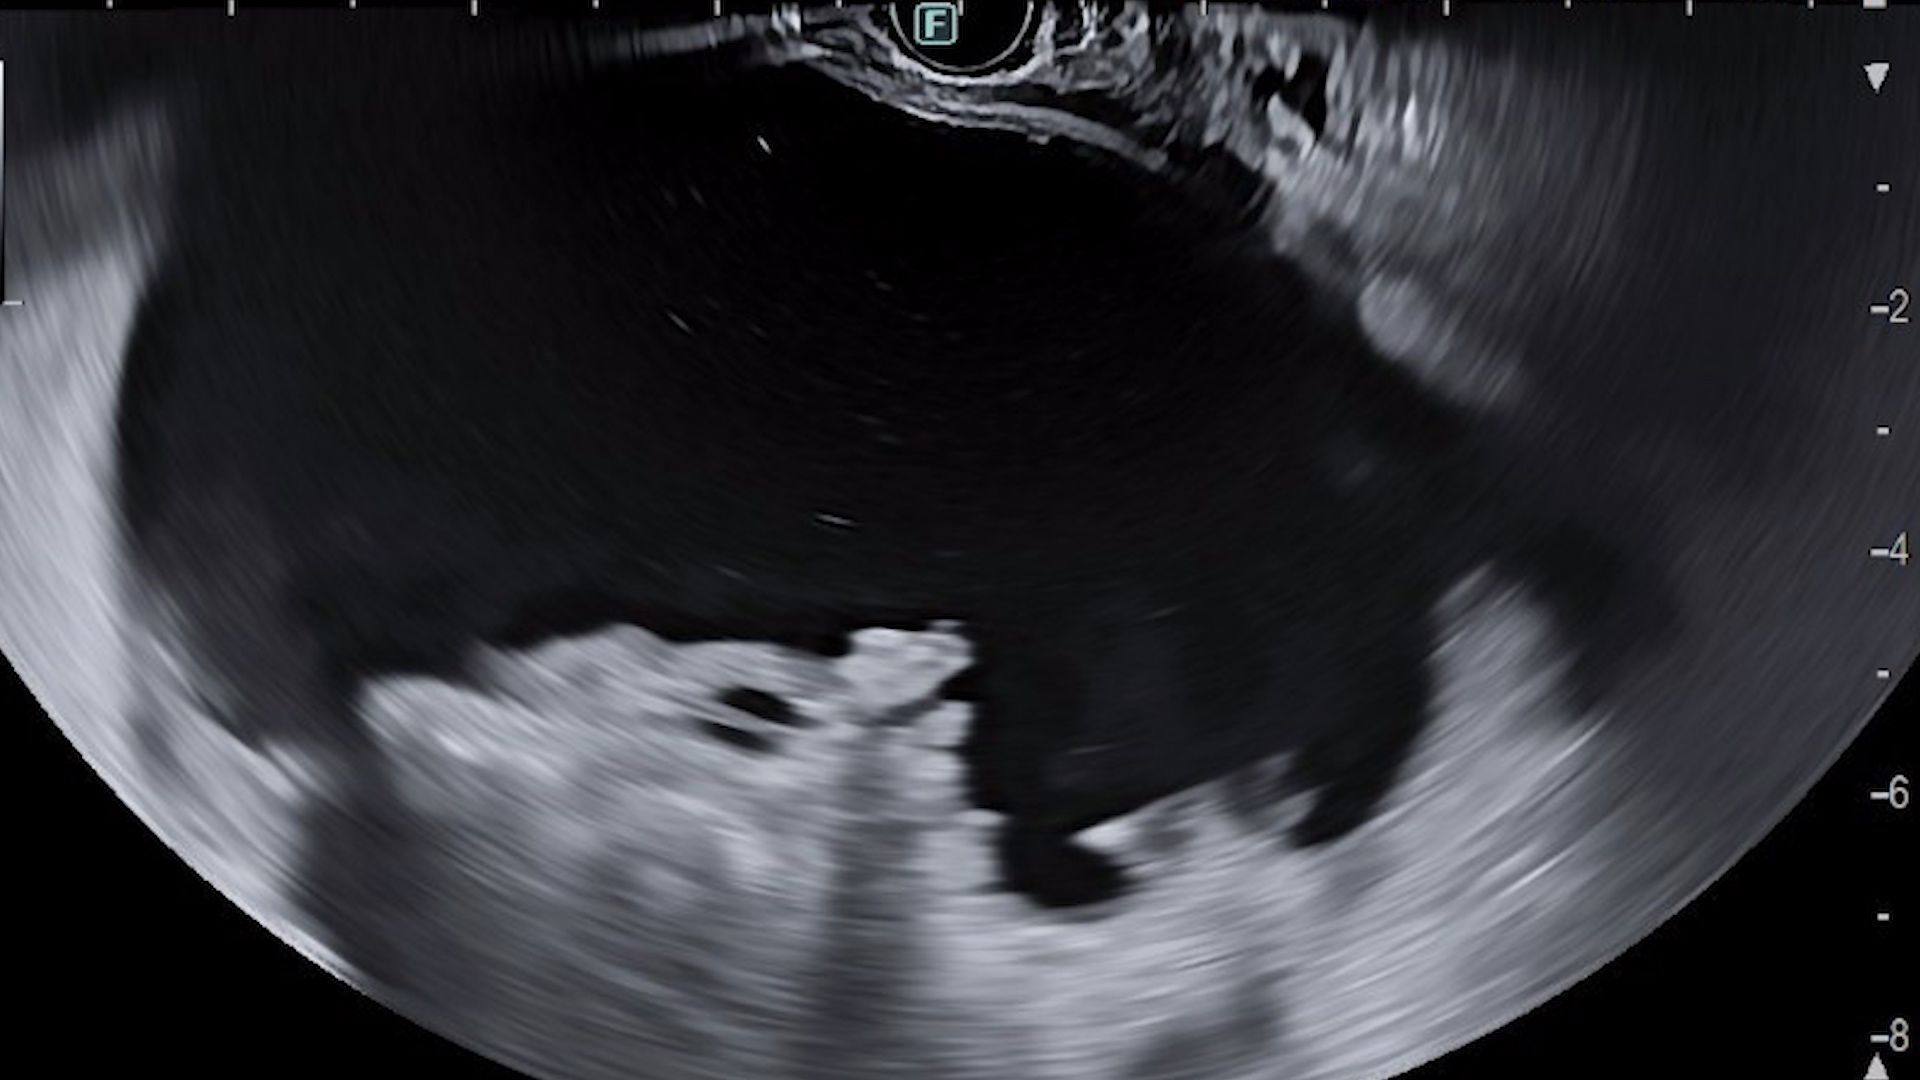

Drenajul ecoendoscopic:

Examinarea ecoendoscopică evidențiază colecție peripancreatică de mari dimensiuni (12/7/6 cm) cu zone hiperecogene declive, cu aspect sugestiv pentru necroză (Film 1). S-a efectuat puncție ghidată EUS cu ac FNA 19G și s-a aspirat lichid brun. Ulterior, sub ghidaj EUS și ghidaj radiologic, s-a montat transgastric stent tip LAMS (HotAXIOS, Boston Scientific) 15 mm pe fir ghid 0,035 Fr, cu drenajul a cca. 1000 mL lichid brun (Fig. 3-4). Ulterior s-a introdus un stent dublu pigtail prin stentul metalic LAMS (Fig. 5).